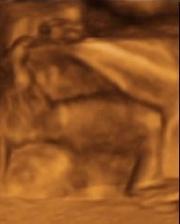

19.3.2010 - 4D utz - Byl to úžasný zážitek. Davídek se sice nejdřív nechtěl ukázat, ale nakonec si dal říct a pootočil se a ukázal nám jeho krásný obličejík 🙂)) je jak panenka s naducanýma tvářičkama 🙂)